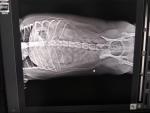

Сделали рентген и анализ крови.

Сказали, что немного увеличена печень и чуть повышены лейкоциты в крови. Есть воспаление в организме (может слизистая кишечника воспалилась из-за того, что шла по нему непереваренная трава?) Амилаза в порядке. Я всё-таки склоняюсь к тому, что у него были кишечные колики из-за травы.